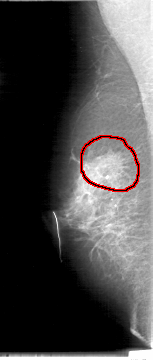

D_4007_1.RIGHT_MLO

FILE: D_4007_1.RIGHT_MLO.OVERLAY

TOTAL_ABNORMALITIES 1

ABNORMALITY 1

LESION_TYPE MASS SHAPE IRREGULAR MARGINS SPICULATED

ASSESSMENT 0

SUBTLETY 4

PATHOLOGY MALIGNANT

TOTAL_OUTLINES 1

BOUNDARY